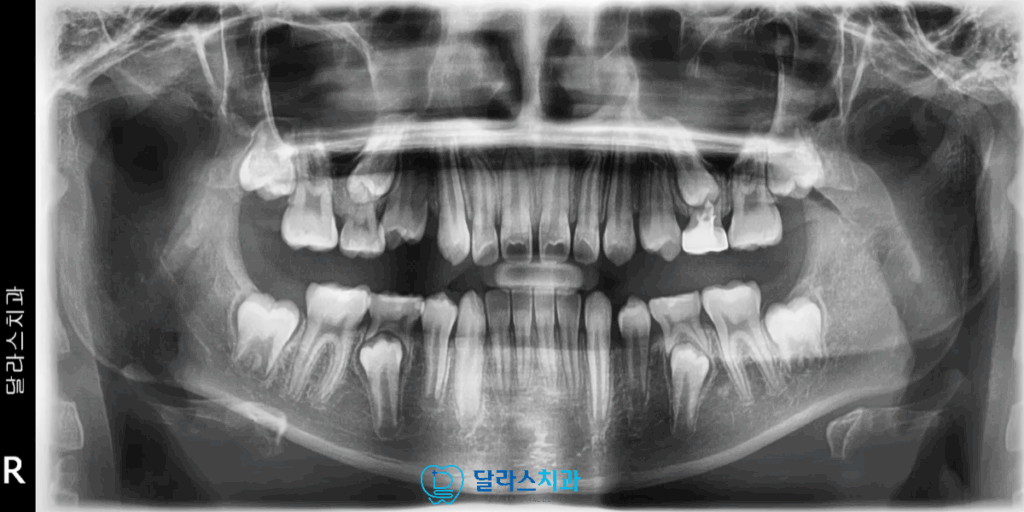

또한 아직 유치가 남아있는 혼합치열기의 상태였기 때문에

유치가 자연스럽게 빠지면서 맹출되는 영구치로 인해 자주 바뀌는 구내환경이었습니다.

그리고 상악의 돌출과 함께 아래턱의 발육이 다소 부족한 치열과

치조골성장에서 복합적인 문제를 보였기 때문에 발치를 진행하는 것보다는

성장 잠재력을 활용하여 바른 교합과 안모 개선을 유도하는 방향이 적절하여

성장기 단계에서 시도할 수 있는 Invisalign Firtst로 교정을 진행하기로 하였습니다

기존에는 앞니가 상당히 앞쪽으로 나가있고 하악이 뒤로 들어가있었던 반면

교정 마무리 후 적절한 거리에서 정상범위내의 수준으로 피개가 되는 것을 확인할 수 있습니다.